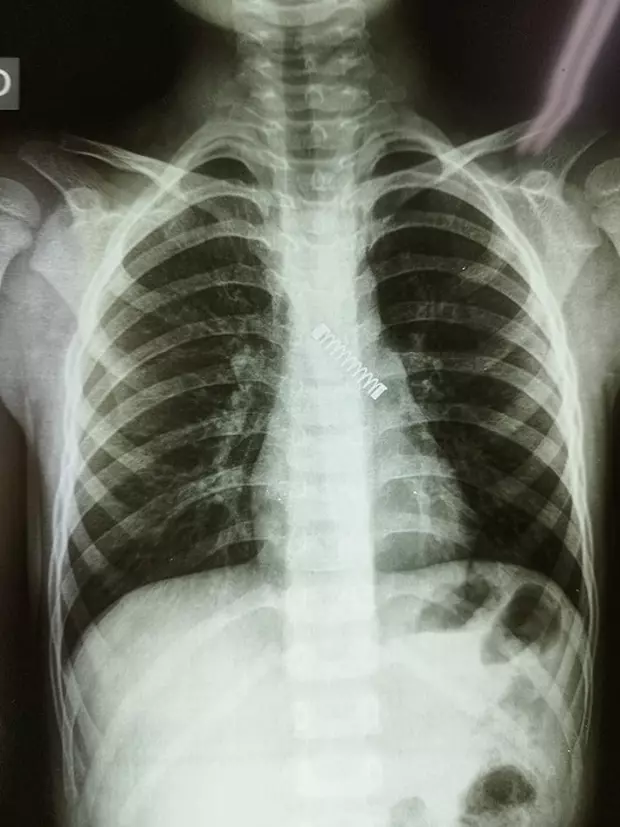

În timp ce efectuau verificări ample pentru a detecta problema, medicii au fost uimiți să găsească un obiect metalic, mai exact arcul unui pix, în plămânul stâng al copilului. Obiectul a fost vizibil pe radiografie.

Cu toate acestea, în ciuda faptului că obiectul a dus la o „scădere probabilă' a capacității plămânilor, doctorul Morinigo a precizat că starea plămânilor se va îmbunătăți pe măsură ce băiatul va crește. Medicul a postat pe rețelele de socializare câteva fotografii cu arcul de pix din plămânul băiatului.